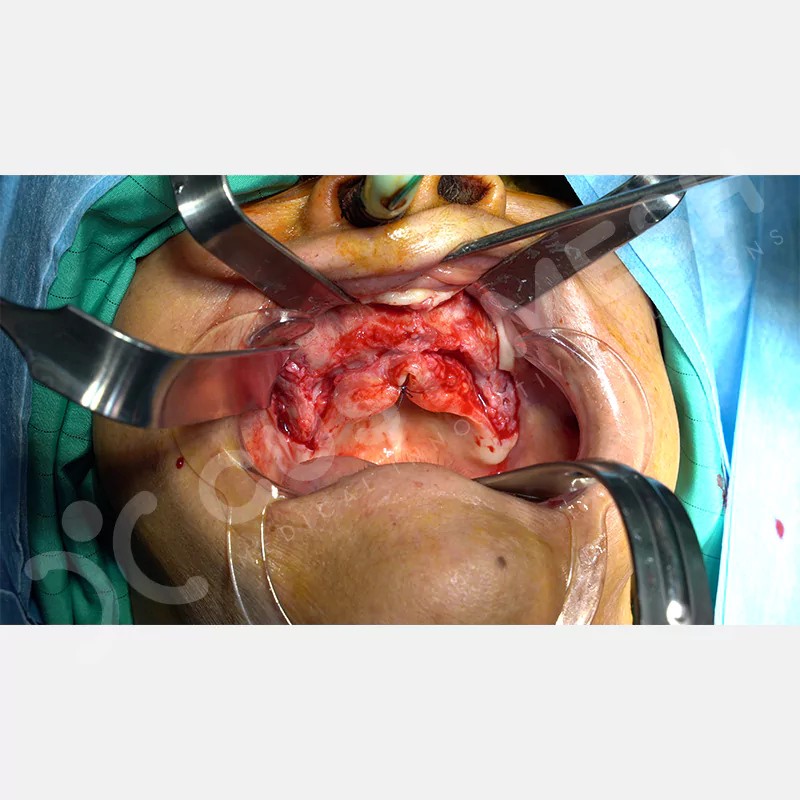

Modern diş hekimliğinde, çene gelişimini tamamlamamış veya ciddi kemik kaybı yaşayan hastalar için kişiye özel titanyum implantlar ile çözüm bulunmaktadır. CAD/CAM teknolojisi ve lazer sinterleme yöntemiyle üretilen bu implantlar, hastanın bireysel anatomik yapısına tam uyum sağlayarak geleneksel implantların uygulanamadığı vakalarda mükemmel bir alternatif oluşturmaktadır. Özellikle ileri derecede kemik kaybı olan hastalar için geliştirilen subperiosteal implantlar, periostun altına yerleştirilerek minimal invaziv bir yaklaşım sunarken, bilgisayarlı tomografi verileri ve sonlu eleman analizleriyle optimize edilmiş tasarımları sayesinde hem estetik hem de fonksiyonel sonuçlar garanti etmektedir. Bu yenilikçi teknoloji, tek seansta implant ve protez uygulamasına imkan vererek hastaların aynı gün doğal gülüşlerine kavuşmalarını sağlarken, kemik greftleme gibi ek işlem ihtiyacını ortadan kaldırarak cerrahi süreci büyük ölçüde kolaylaştırmaktadır. Kişiye özel tasarımı ve üstün biyouyumluluğu sayesinde, daha önce tedavisi mümkün görülmeyen kompleks vakalarda bile başarılı sonuçlar sunan bu implantlar, modern diş hekimliğinde yeni bir çağ açarak hastaların yaşam kalitesini artırmayı hedeflemektedir.

VAKA 1

VAKA 2

VAKA 3

VAKA 4